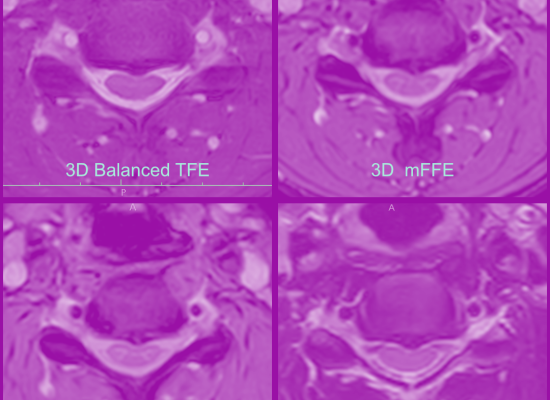

007 Axiale T2-gewichtete Schichten in der HWS (1.5T Philips)